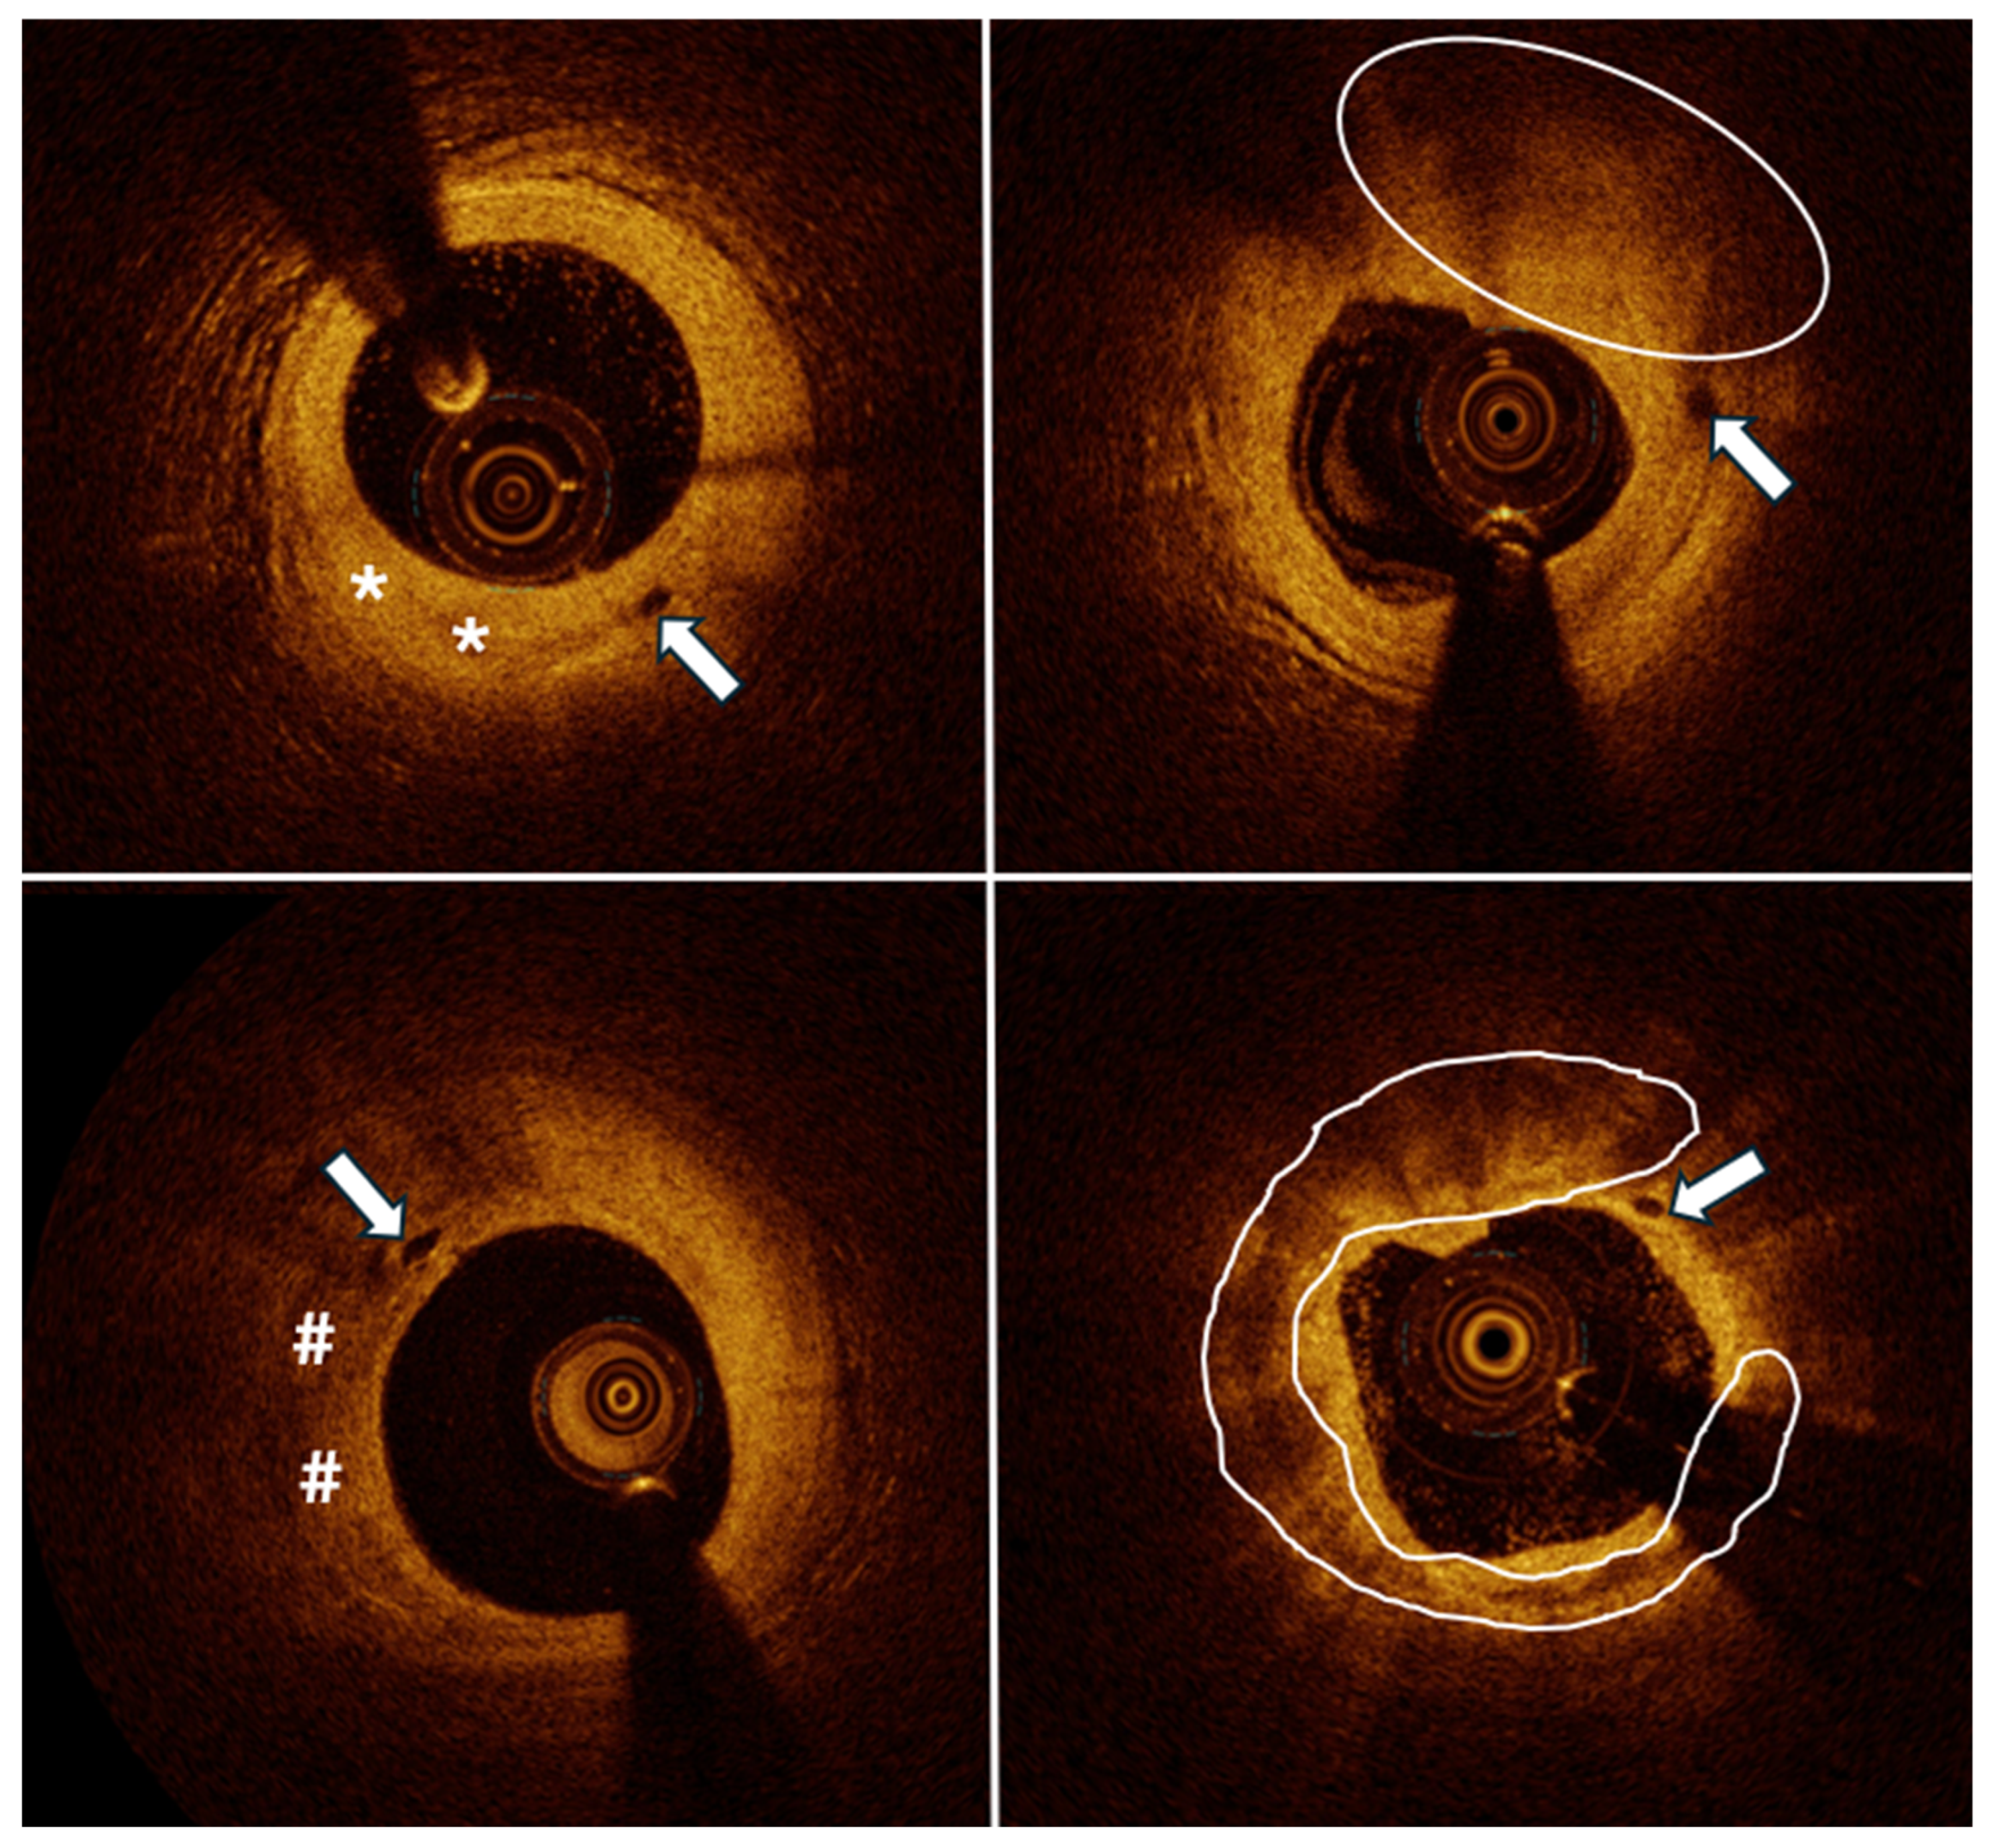

:1. Introduction

2. Materials and Methods

3. Results

4. Discussion